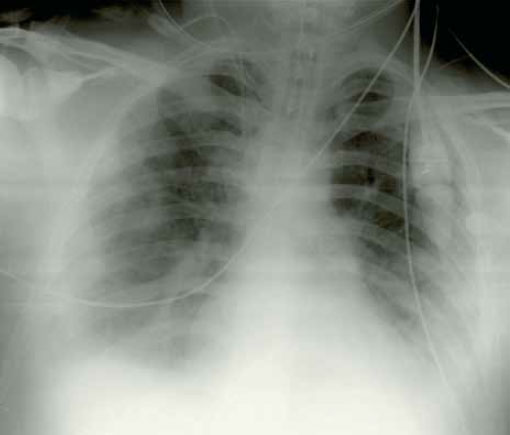

В случае поражения легкого ударной волной положительные результаты рентгенографии обычно наблюдаются не позднее 4 часов, и проявляются они в виде легочной непрозрачности — инфильтратов, которые классически описываются как рисунок «мотылек» (рисунок 4). Как правило, они достигают максимума через 24—48 часов, а затем у выживших они постепенно рассасываются в течение 7 дней. Развитие инфильтратов по прошествии 48 часов указывает на острую дыхательную недостаточность или на пневмонию (см статью «Рентгенография: Пневмония»).

Рисунок 4. Рисунок «мотилька» при двустороннем легочном инфильтрате. На рентгенограмме наблюдаются центральные уплотнения, сходные с ушибом легочной паренхимы